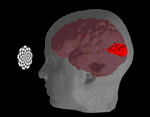

Die folgende Grafik zeigt zusammenfassend noch einmal die drei wichtigsten Hirnregionen unseres Lust-, Belohnungs- und Glückssystems, beispielsweise während wir lachen:

Nucleus accumbens und linker Stirnlappen, während wir lachen

Copyright © 2002 by Journal of the Neuroscience, USA